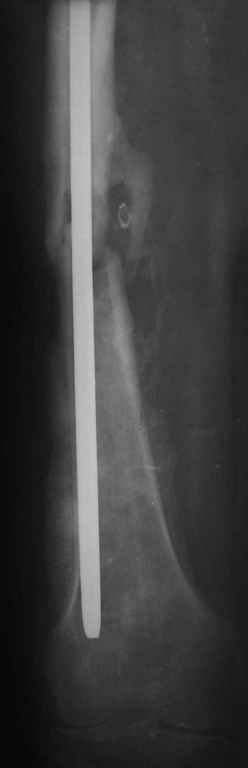

Мы не дождались “Happy End”, у больного IQ в пределах 70%, через 6 месяцев вернулся после небольшой травмы, споткнувшись получил перелом

того же бедра (рис №7).

При обзоре причин перелома, на снимке №2 обнаружили, что один из стержней аппарата наружной фиксации проходил только через передний кортекальный слой, что создало стрессовую зону на бедре и в результате перелом из-за незначительной травмы.

На снимке N2 виден канал от стержня во фронтальной плоскости, на уровне которого на снимке N7 уже перелом.